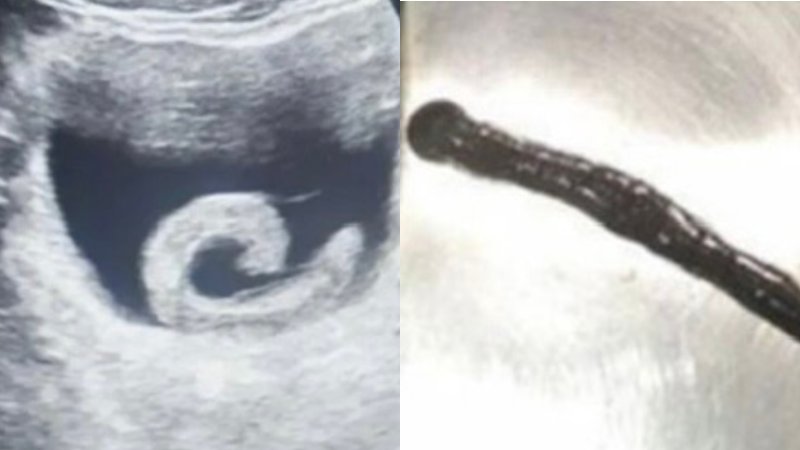

당시 남성은 얼굴이 창백한 상태로 식은땀을 흘리며 허리를 굽힌 채 복부를 움켜쥐고 있었고, 의료진은 초음파 검사를 통해 방광 내부에서 움직이는 띠 모양의 이물질과 출혈을 확인했다.

비뇨기과 의료진이 방광경 검사를 실시한 결과, 길이 약 5~6㎝의 거머리 한 마리가 방광 점막에 붙어 있는 것이 발견됐다.

의료진은 즉시 내시경을 통해 피를 잔뜩 빨아 부풀어 오른 거머리를 요도를 통해 제거했고, 시술 직후 환자의 통증은 사라졌다.